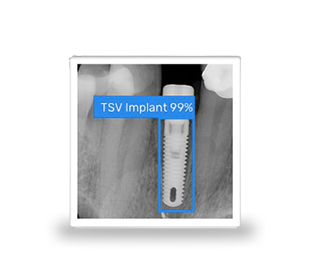

Identificar un implante dental

Nuestra tecnología de IA identifica su implante dental a partir de una simple radiografía periapical.